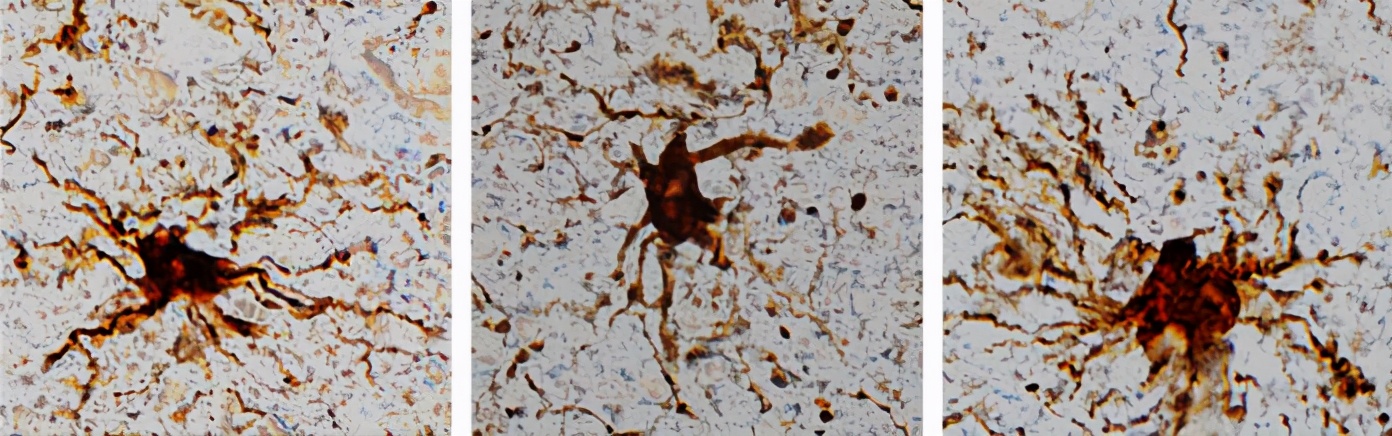

研究人员收集了常规脑手术的新鲜脑组织,对这些脑组织进行切除,并进行多次模拟人死后的间隔。结果,他们就发现,在这些脑组织当中,有一部分细胞中的基因没有停止表达,而且还在增加表达。于是,他们把这些死后还会表达的基因称之为:僵尸基因。这些僵尸基因在人死后大脑的神经胶质细胞当中。(神经胶质细胞的工作主要是:在脑损伤之后,进行清理。)

僵尸基因的表达可以促使神经胶质细胞持续地生长好几个小时,并且长出“长臂状”的附属物。在人死后的12个小时左右达到活性的最高峰。